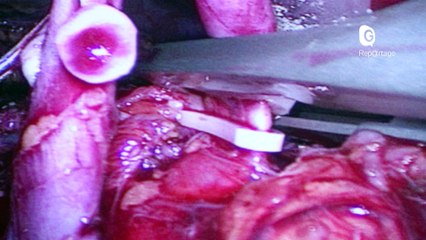

FEMME ACTUELLE - Le témoignage bouleversant du petit Imad, 8 ans, greffé d’un rein